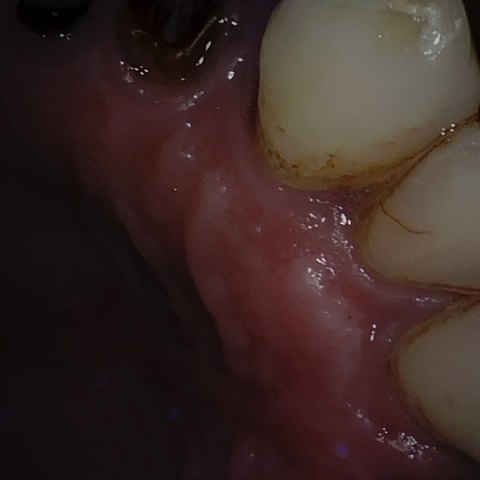

Annotated as "Good"